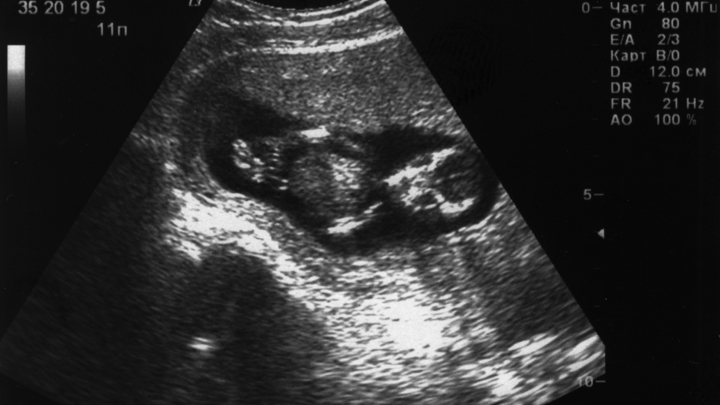

Врач рассказал, как работает мозг беременных женщин

Во время беременности женщины могут стать забывчивыми, однако решают задачи не хуже, чем раньше. Таковы данные современных исследований.

Михаил Тонев, ведущий врач-невролог клиники "Ниармедик" на Маросейке, рассказал "Газете.Ru", что происходит с мозгом беременной женщины.

Из-за увеличения отделов, отвечающих за эмоции, будущие матери становятся более экспрессивными. Другие отделы мозга, например, отвечающий за кратковременную память гиппокамп, уменьшаются. Это объясняет забывчивость и рассеянность многих беременных.

Однако функционал всех отделов мозга остаётся неизменным, то есть ни о какой "утечке мозгов" речи не идёт. Женщины не начинают хуже решать задачи, так что это не более, чем распространённое заблуждение,

- подчеркнул Тонев.

Есть также исследования, согласно которым в некоторых областях мозга при беременности несколько снижается количество серого вещества. Однако это - не патологический процесс, а необходимое условие адаптации женщин к новой роли и формирования привязанности к младенцу, резюмировал невролог.